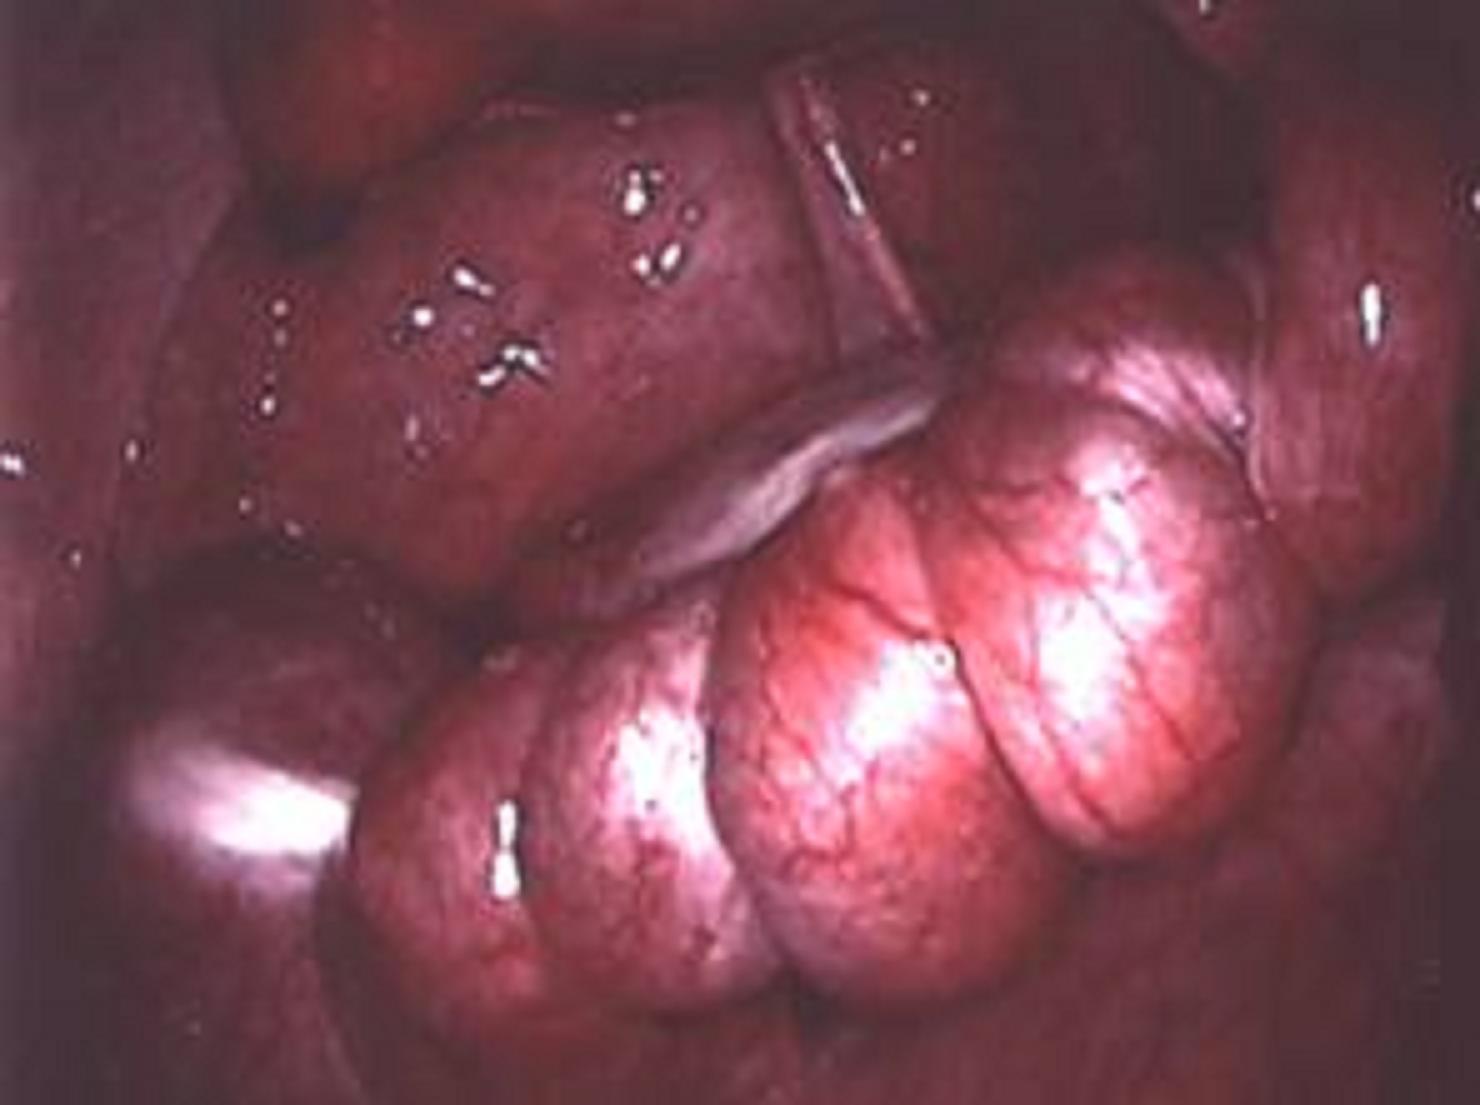

Vue cœlioscopique d'une torsion d'annexe